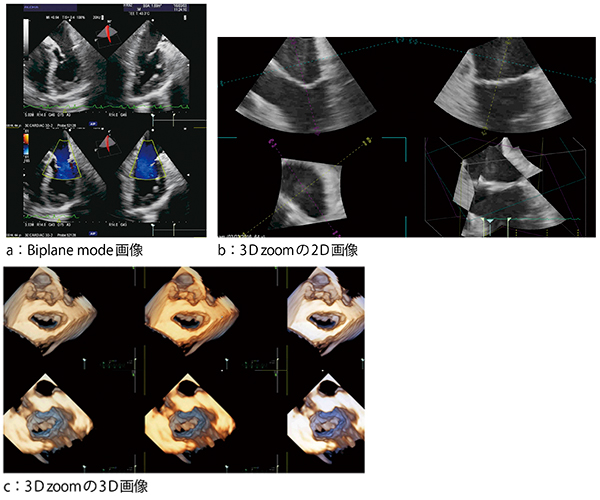

図1 aは,Biplane modeによる僧帽弁の画像で,心尖四腔像と直交する二腔像を同時に表示している。僧帽弁を関心領域に設定して3D zoomで画像を作成するが,画像は1 beatで取り込んでおり,そこから切り出した2D画像(図1 b)と3D画像(図1 c)が表示される。図1 c上段はSurgeon’s View(左房側から見る僧帽弁の像),図1 c下段はLV Viewであるが,それぞれ3つの画像は同じ画像の色付けを変えて表示したもので,配色は変更可能である。

図1 僧帽弁の3D TEE画像

大動脈弁のBiplane modeの画像(図2 a),および3D zoomの2D画像(図2 b)と3D画像(図2 c)を示す。図2 cは大動脈弁を大動脈側から見ており,左冠動脈,左冠尖,右冠尖,無冠尖が確認できる。

図2 大動脈弁の3D TEE画像